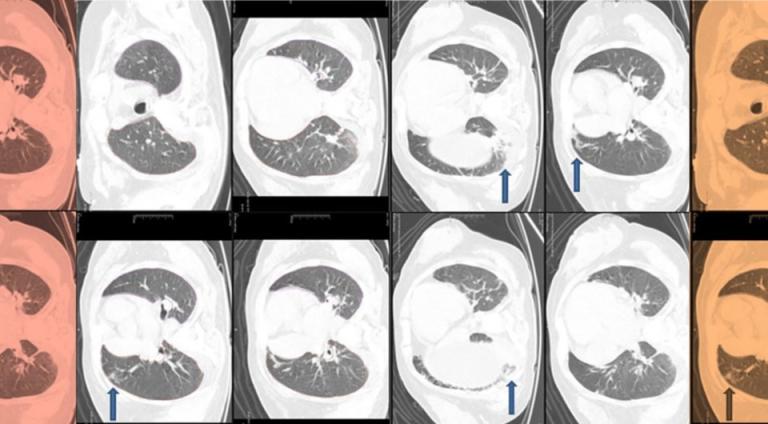

- Ультразвук и компьютерная томография выявили увеличение печени со стеатозом и циррозом, а также фиброзные изменения в легких.